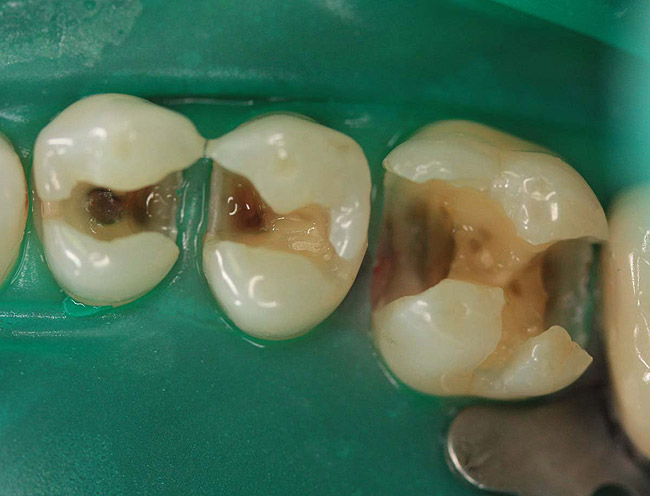

Case 2 (Figure 7 through Figure 11) depicts a series of defective amalgams on the first molar and biscupids. The amalgams were removed, the decay was excavated and cracks were eliminated. Bonding was completed on dentin and enamel. The teeth were matrixed and composite was built with layering techniques. To control contours, each tooth was completed individually, and then the next one was done. Composite was shaped, occlusal adjustment was completed, and final polishing was done.

Figure 7. Three defective amalgams and cracks on the first molar and bicuspids.

Figure 7

Figure 8. Teeth after removal of amalgams.

Figure 8

Figure 9. Prepared teeth after removal of decay and cracks.

Figure 9